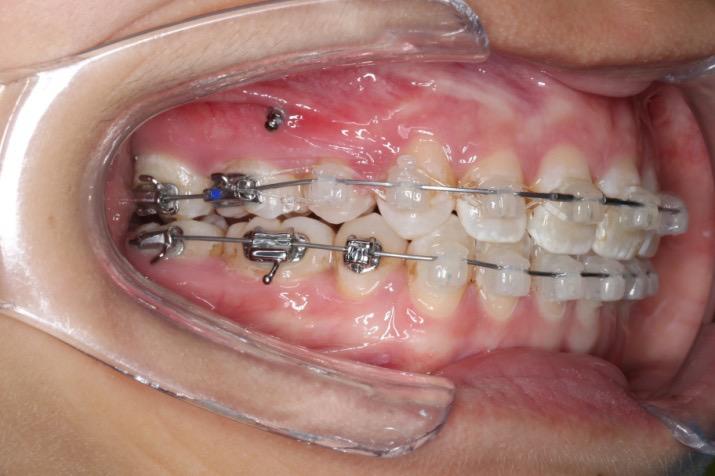

2017.10.07

2017.10.07  继续关间隙,下颌使用水平关间隙

下颌磨牙通过powerarm直立效果明显,下颌整平效果明显

2017.12.15  继续关间隙

2018.03.01上TPA加17、27颚侧牵引钩,压低17、27颚尖下颌43、32重粘,下颌0.016*25niti

2018.04.20  间隙基本关闭,上颌重新整平,精调